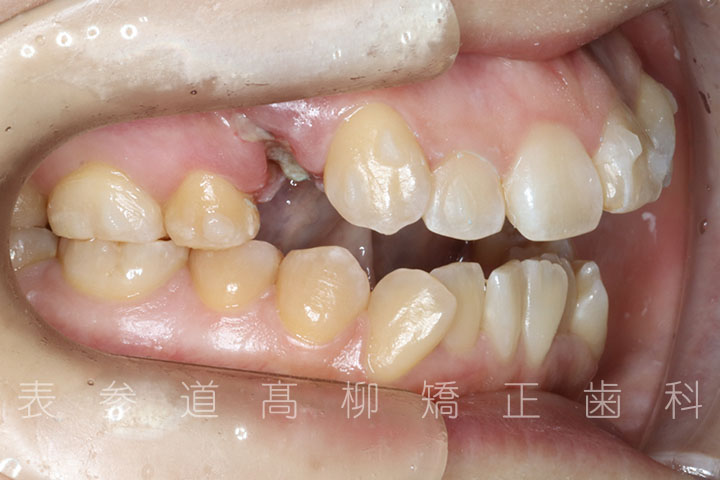

前歯のガタガタ感と開咬でお悩みの患者様の症例をご紹介いたします。

・前歯部開咬

・上下前歯部叢生(凸凹歯並び)

・上顎左右第一小臼歯、下顎左右第二小臼歯を抜歯の抜歯